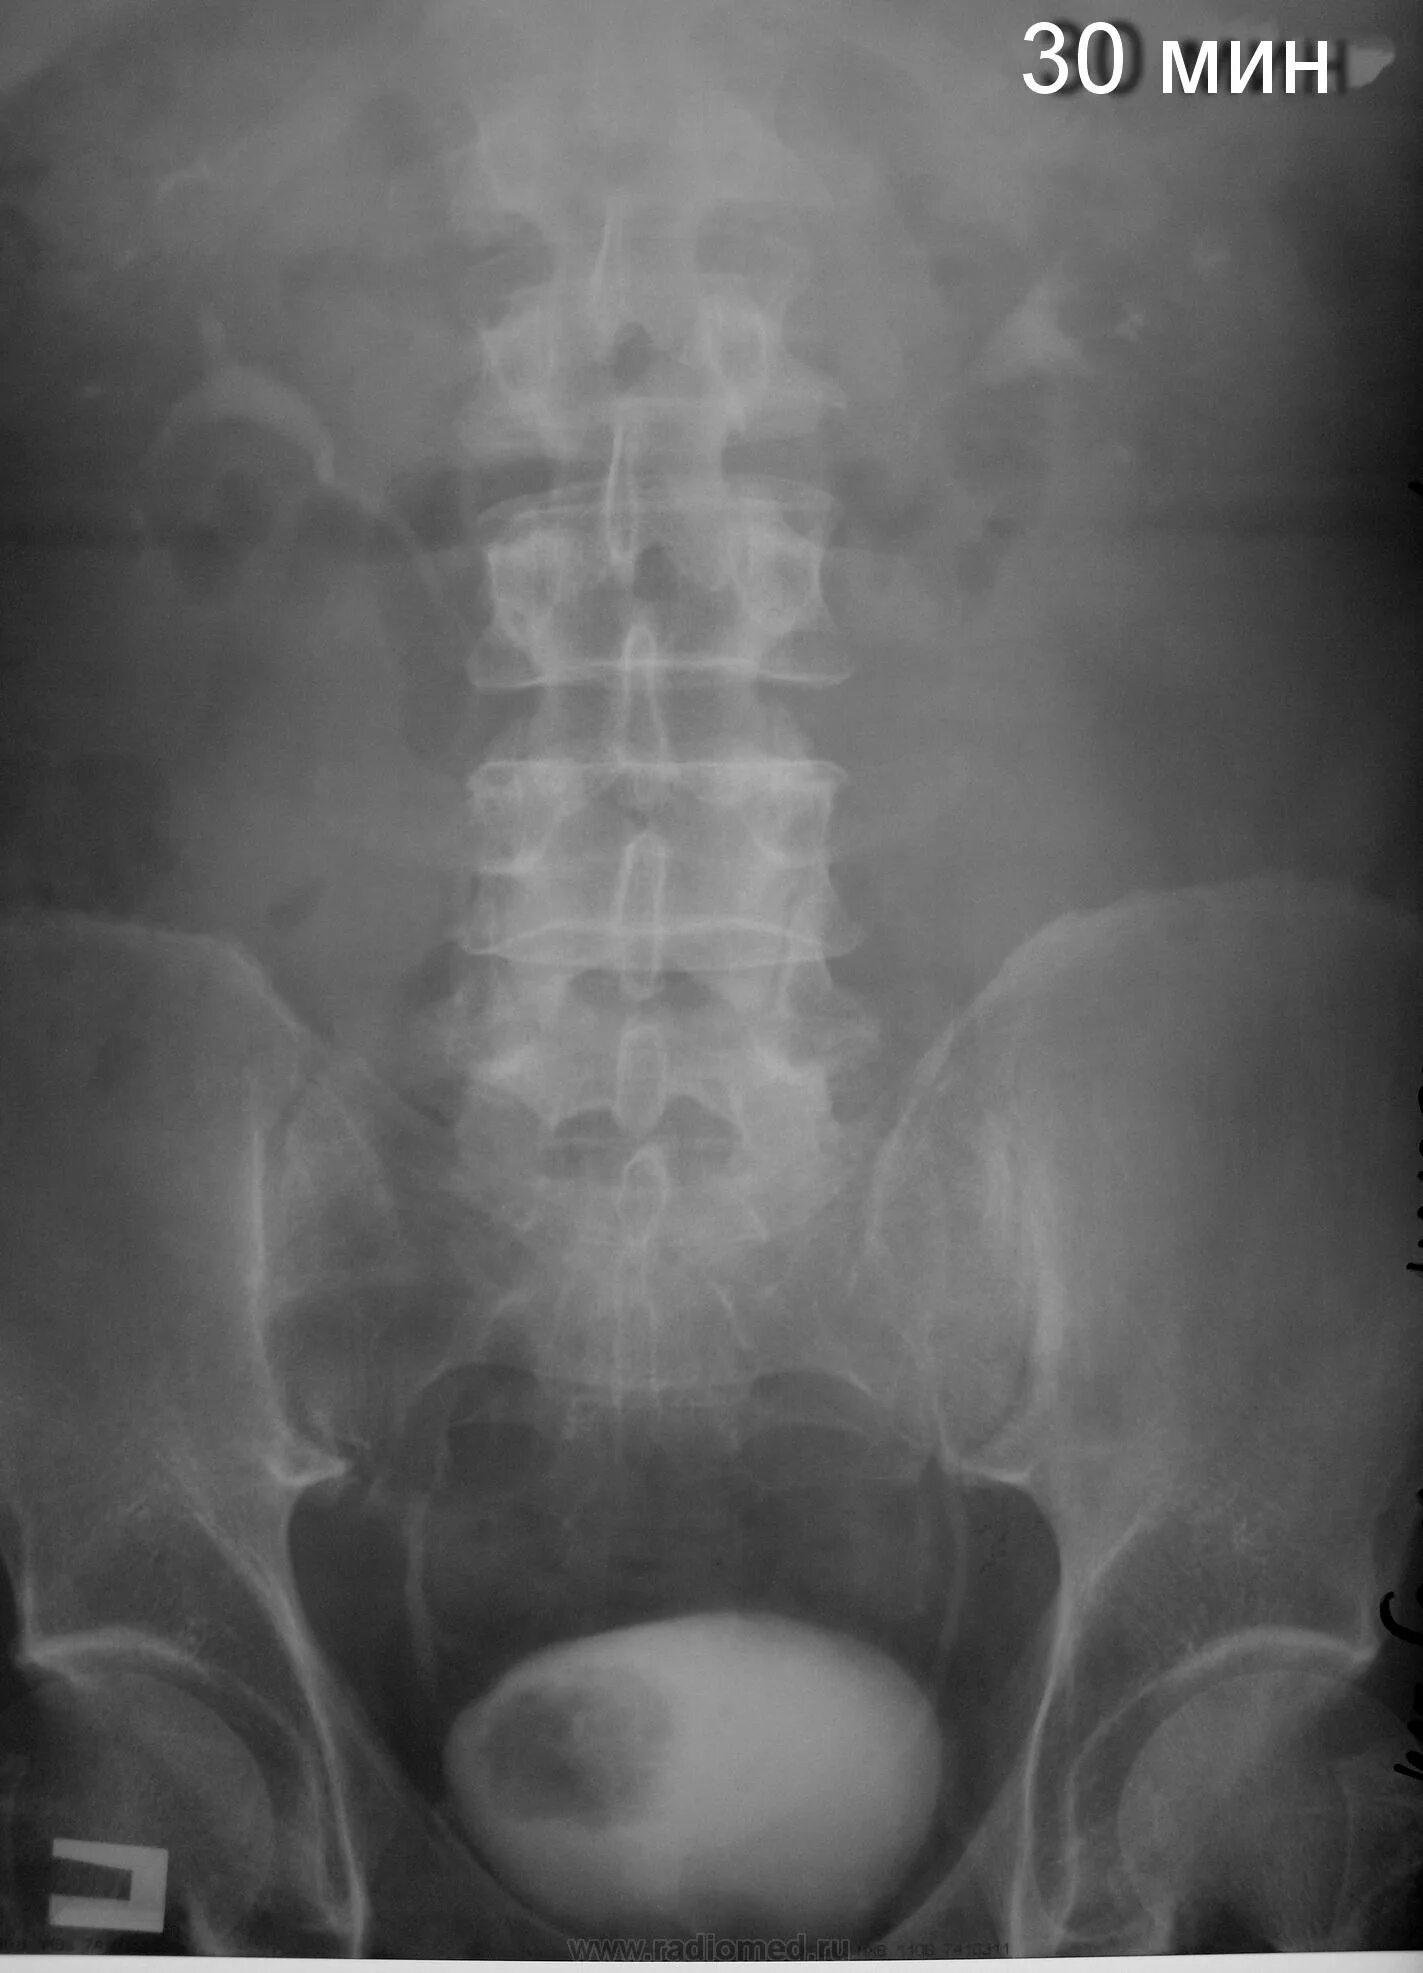

После урографии